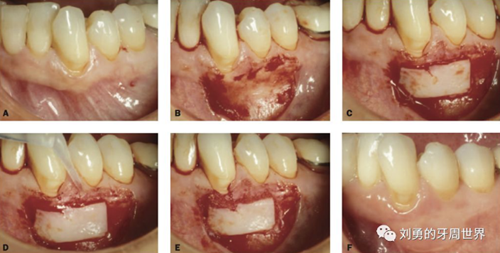

原因是:附著齦增寬的手術(shù),受區(qū)骨膜面積大,血供好,因此用偏薄的就可以,而對于根面覆蓋的手術(shù),受區(qū)外露根面沒有骨膜,血供差,因此取厚一點(diǎn)的,容易成活,對于牙槽嵴缺損的,建議取厚的,不是為了血供,而是為了更明顯的修復(fù)牙槽嵴的缺損。如下圖:

上面是附著齦增寬,因此取的薄一些。

上圖B23頰側(cè)牙槽嵴水平向塌陷明顯,為了增寬,取厚一點(diǎn)的齦瓣效果更好。